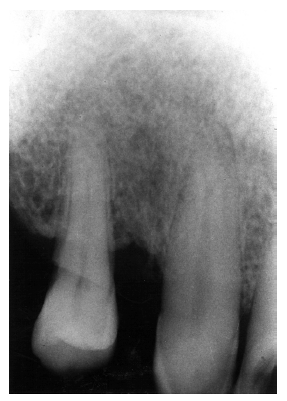

Figure 2 illustrates advanced enamel caries on the mesial surface of the premolar.

Figure 2 - Advanced Enamel Caries

Figure 2